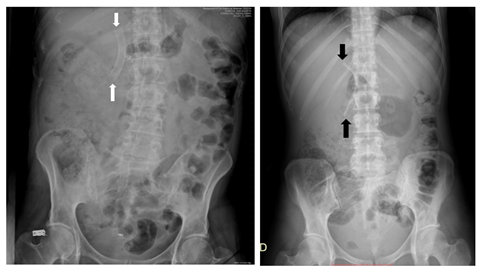

Although biliary prostheses can be evaluated by conventional radiographic studies (Figure 2), computed tomography (CT) has several distinct advantages over them in the visualization of the migrated stents and in the diagnosis of associated complications. Multidetector Computed Tomography (MDCT) provides high-resolution images not only of the endoprosthesis, but also of the wall of the biliary or enteric segments where the stent and surrounding fat planes, organs and other abdominal structures are located. While endoscopy and conventional radiography show only intraluminal changes, CT can be used to visualize extraluminal signs of complications such as free peritoneal air, retroperitoneal gas, or liquid collections. The major limitations of MDCT are the radiation dose, which is cumulative, and the high cost, especially if this imaging technique is performed only for the evaluation of a permanent stent.19

Figure 2 Simple X-rays of abdomen of other patients, with well-positioned metallic (white arrows) and plastic (black arrows) biliary stents.